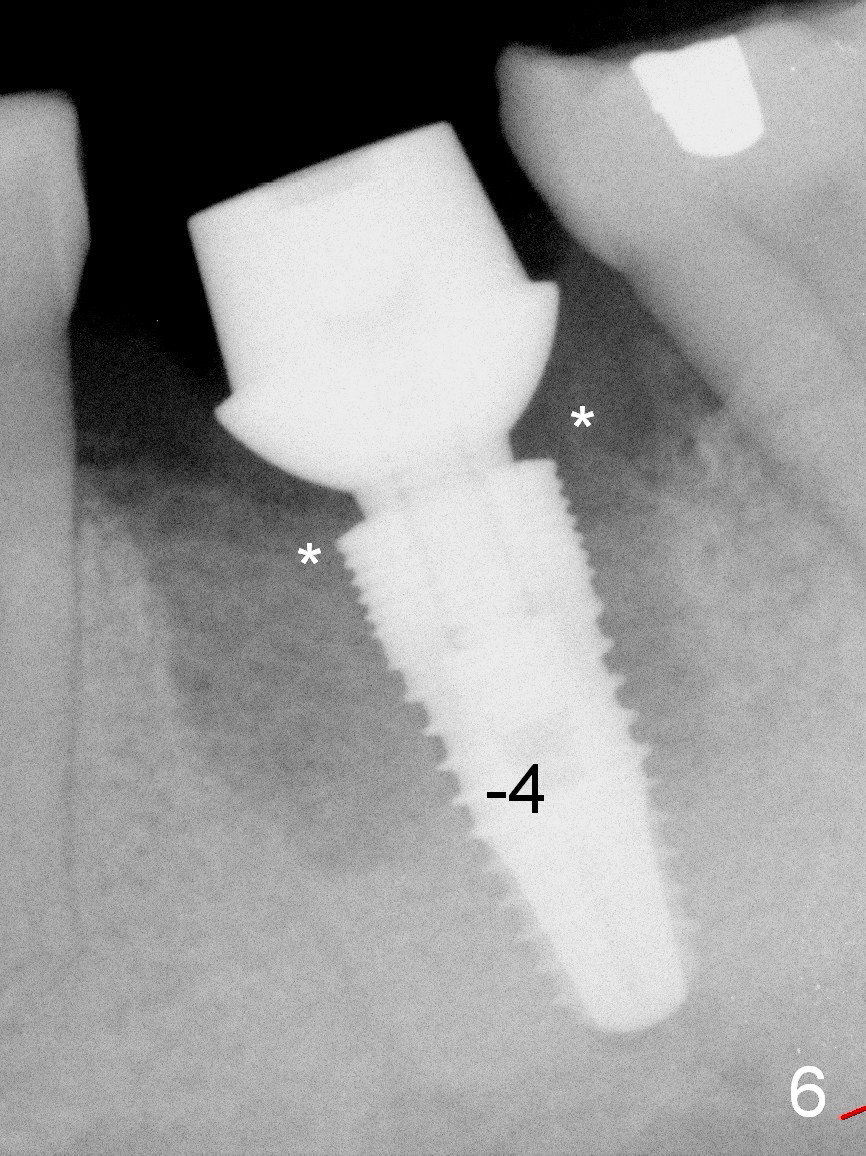

After 5 mm drill is used, the implant is seated deeper with insertion torque < 35 Ncm (Fig.6).  It suggests overprep.  Anyway, an immediate provisional is fabricated after placement of an abutment (7.8x4(3) mm).  After reline, the provisional fits well.  It has to be removed with forceps for occlusal adjustment.  Finally the abutment/implant complex turns in the socket with fingers.  The rotation/position of the complex is randomly adjusted.  When the provisional is cemented, it does not seat completely, but is stable.  If the implant osteointegrates, the provisional must play a role in stabilizing the implant.  Bone graft is placed in the gap prior to cementation (Fig.6 *).  Postop analysis of PAs in Fig.6,7 (1.5 month postop) shows that the peri-implant defect has been reduced in 1.5 months.  Immediately postop, the fourth coronal large thread is buried in the solid bone, whereas 1.5 months postop the third thread appears inside the base bone.  Bone density increases in the peri-implant space 16 months post cementation (Fig.10) and continues to increase 2 years 8 months post cementation (Fig.11).